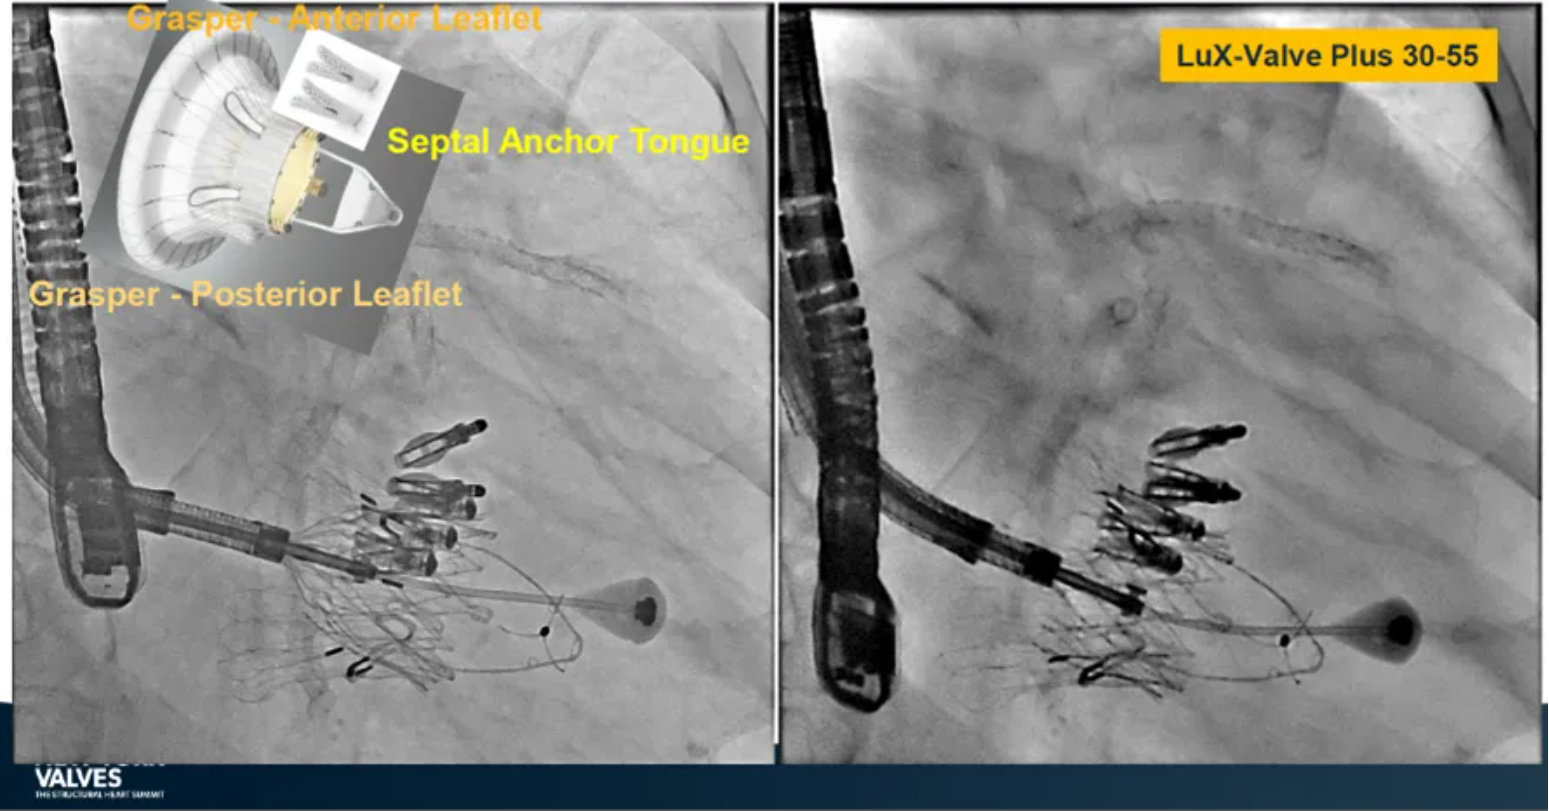

LuX-Valve Plus是健世科技(Jenscare,9877.HK)推出的全新一代經頸靜脈三尖瓣置換系統(Transjugular Tricuspid Valve Replacement System),其創新性地采用頸靜脈作為手術入路,在不依賴徑向支撐力的情況下借助室間隔錨定、瓣葉夾持技術構成其多重錨定結構,并通過自適應編織環有效進行心房側封堵,呈現更好的安全性和有效性。

來自中國香港瑪麗醫院(Queen Mary Hospital, Hong Kong, China)的Simon Lam教授在2024年紐約瓣膜會上分享了一例復雜案例,一名高齡男性患者在2年前行二尖瓣和三尖瓣TEER術式后繼發三尖瓣反流,遂再次行二尖瓣TEER術式和用LuX-Valve Plus行三尖瓣TTVR術式。

本次術式中,LuX-Valve Plus的植入緊隨二尖瓣修復術式之后,且并未取出前期植入的三尖瓣修復夾,這意味著LuX-Valve Plus在患者有過二尖瓣和三尖瓣修復夾植入情況下的兼容性,并且帶來了有效的治療結果。此外,這不僅體現了LuX-Valve Plus可以與二尖瓣術式并行,更可以兼容三尖瓣原位的其他修復夾產品。